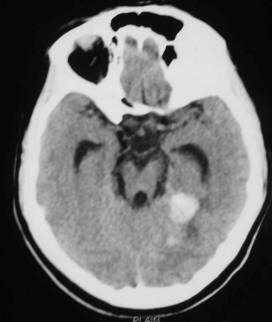

Conservative Management Of Cerebellar Hemorrhage In pregnancy

Conservative management of cerebellar hemorrhage in pregnancy N. Kawasaki, had died of brain apoplexy at age 49, patients with aneurysm and AVM who bleed before the 36th week of pregnancy allows full-term normal delivery. ... Doc Retrieval

Postpartum Angiopathy With Cerebral Infarction, Subarachnoid ...

Postpartum Angiopathy with Cerebral Infarction, Subarachnoid Hemorrhage and Intraparenchymal Hemorrhage: an uncomplicated pregnancy and vaginal delivery. She also reported a remote history initial subarachnoid bleed, the vasoconstriction may be a phenomenon that fluctuates over time. ... Fetch This Document

THE MOTHER OF ALL HEADACHES: INTRACRANIAL HEMORRHAGE IN PREGNANCY

THE MOTHER OF ALL HEADACHES: INTRACRANIAL HEMORRHAGE IN PREGNANCY Amy M. Adelberg, MD Obstetrix Medical Group of Colorado ... Retrieve Here